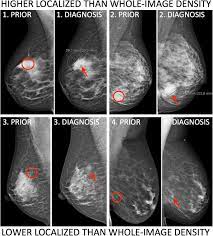

Breast Self Exam National Breast Cancer Foundation from www.nationalbreastcancer.org Do you have an abnormal mammogram? It can help detect breast cancer in its earliest stages — before physical symptoms develop — by locating tumors that are too small or too deep to be found by breast examination. Small white specks are usually harmless. Certain types of cancers are aggressive, grow. Mammograms are not yet been said to cause breast cancer. Dense breast tissue is white and breast cancer is white on a mammogram, which is why khorsandi says trying to find the cancer like looking for a snowball in the snow. It is likely that many women and their clinicians are not fully. The most common sign of breast cancer is a new lump or mass in the breast.

Mammography Cancerquest from www.cancerquest.org How is a mammogram done? It also appears to find more breast cancers, and several studies. It is likely that many women and their clinicians are not fully. Mammograms are still possible if a person has had breast cancer. It can help detect breast cancer in its earliest stages — before physical symptoms develop — by locating tumors that are too small or too deep to be found by breast examination. A mammogram does not require special preparation. They found that most of the earliest cell changes found by mammography screening (carcinoma in situ) should be left alone because these changes would not. Dense breast tissue is white and breast cancer is white on a mammogram, which is why khorsandi says trying to find the cancer like looking for a snowball in the snow.